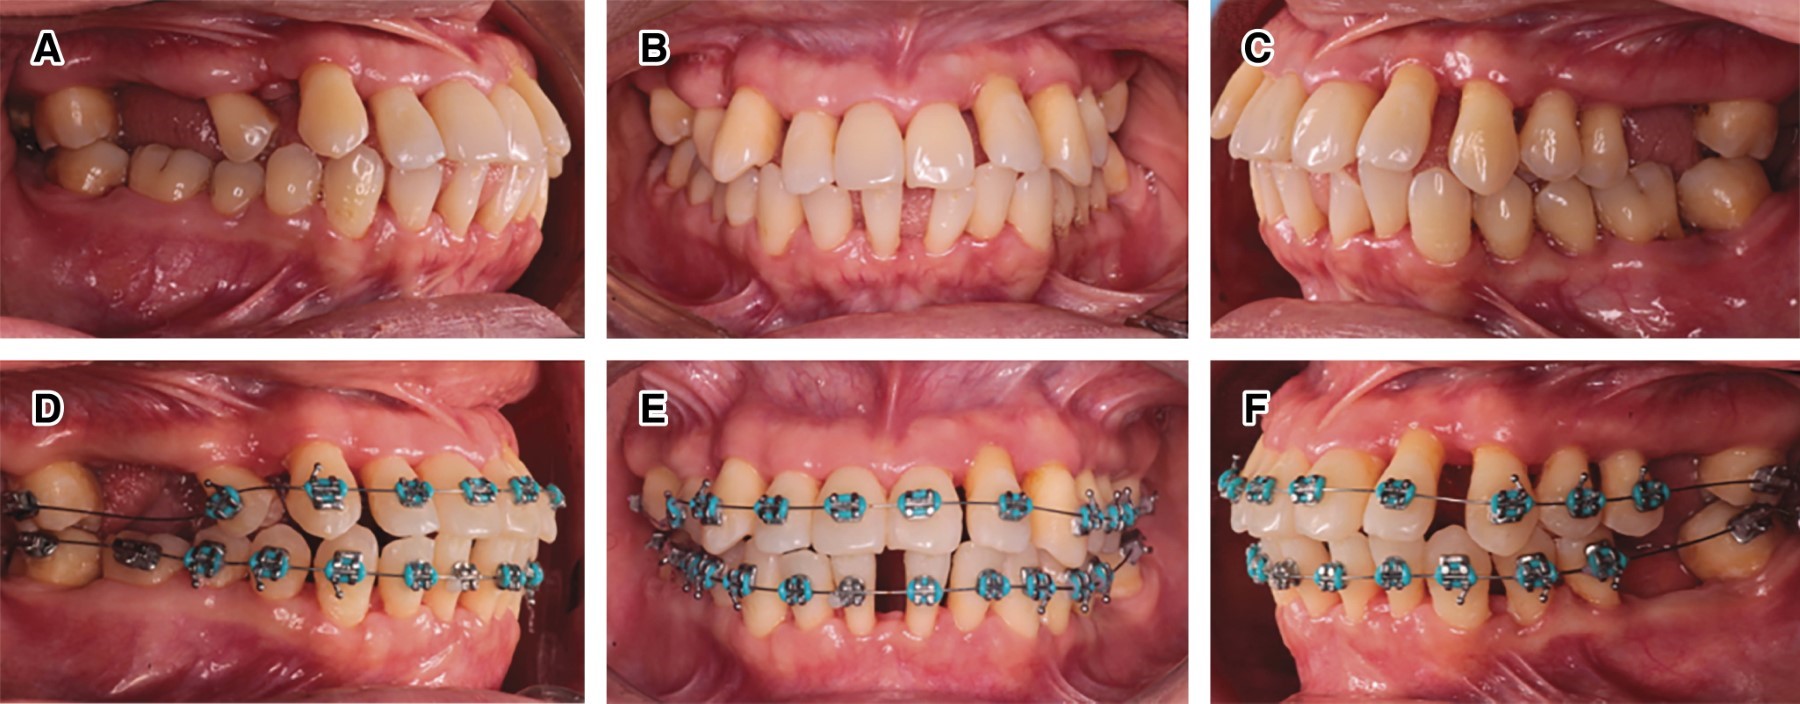

Figure 1